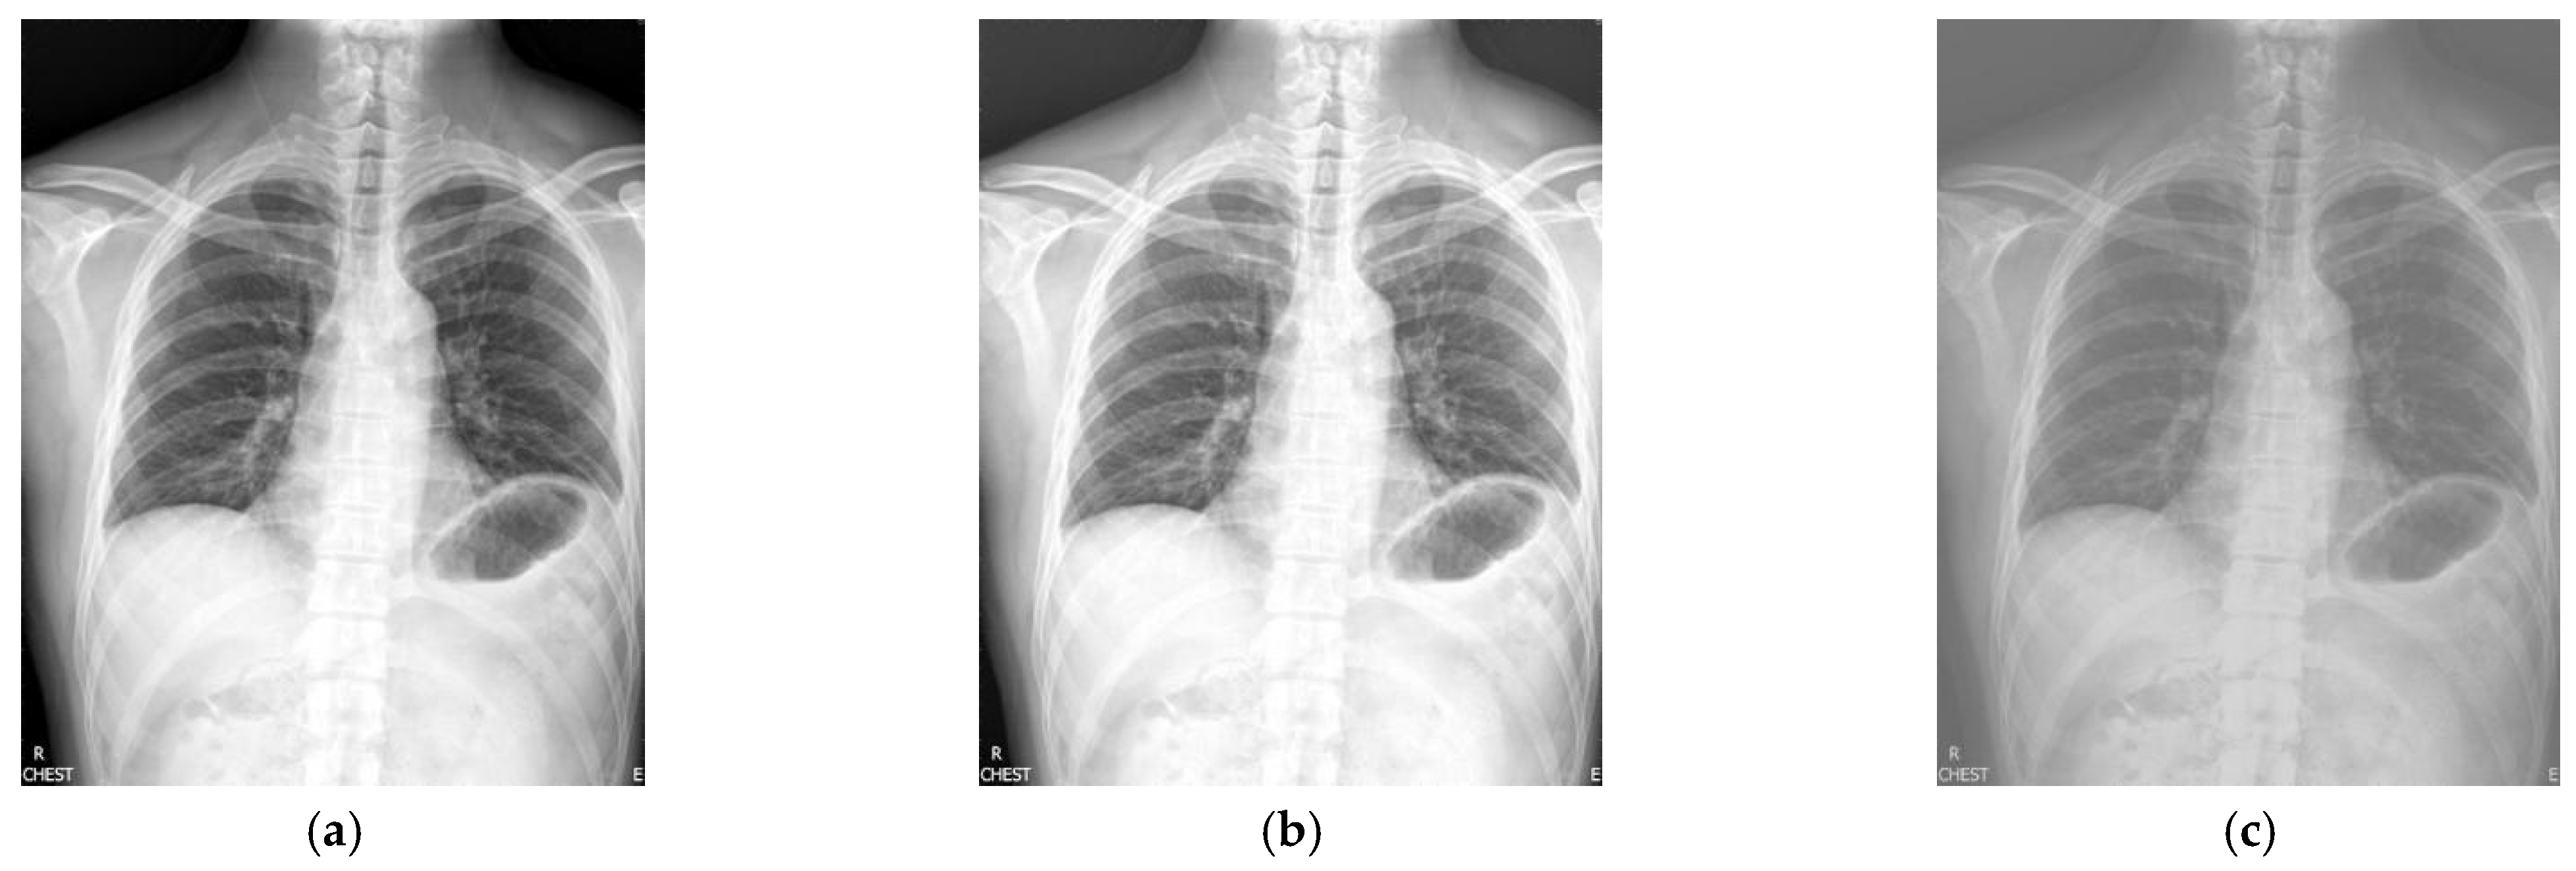

Figure 1 shows the enhancement images of eight methods experimented on X-ray image 1. Figure 1a shows the original X-ray image 1; Figure 1b shows the image obtained by McCann, and the image is too bright; Figure 1c shows the image achieved by RLBHE—the image is too dark and the performance of enhancement is poor, the details of the image are difficult to ascertain; Figure 1d is the result obtained by RESIHE—the definition of the image is low; Figure 1e shows the image enhanced by TBCSSR; Figure 1f represents the image obtained by GDGIF—the image has a lot of noise; Figure 1g and Figure 1h show the result enhanced by SMIPC and FuzzyII, respectively, and the images have poor enhancement performance; Figure 1i is the image achieved by the proposed method—it has moderate brightness and better clarity. Table 1 is the evaluation index values of various algorithms in Figure 1. From this table, we can denote that the values of AG, ALC, SF and MG obtained by the proposed technique are the best; the value of H achieved by SMIPC is the best, and the corresponding value obtained by the proposed method is still ranked second.

Figure 1.

Comparison on X-ray image 1. (a) Original image; (b) McCann; (c) RLBHE; (d) RESIHE; (e) TBCSSR; (f) GDGIF; (g) SMIPC; (h) FuzzyII; (i) Proposed method.